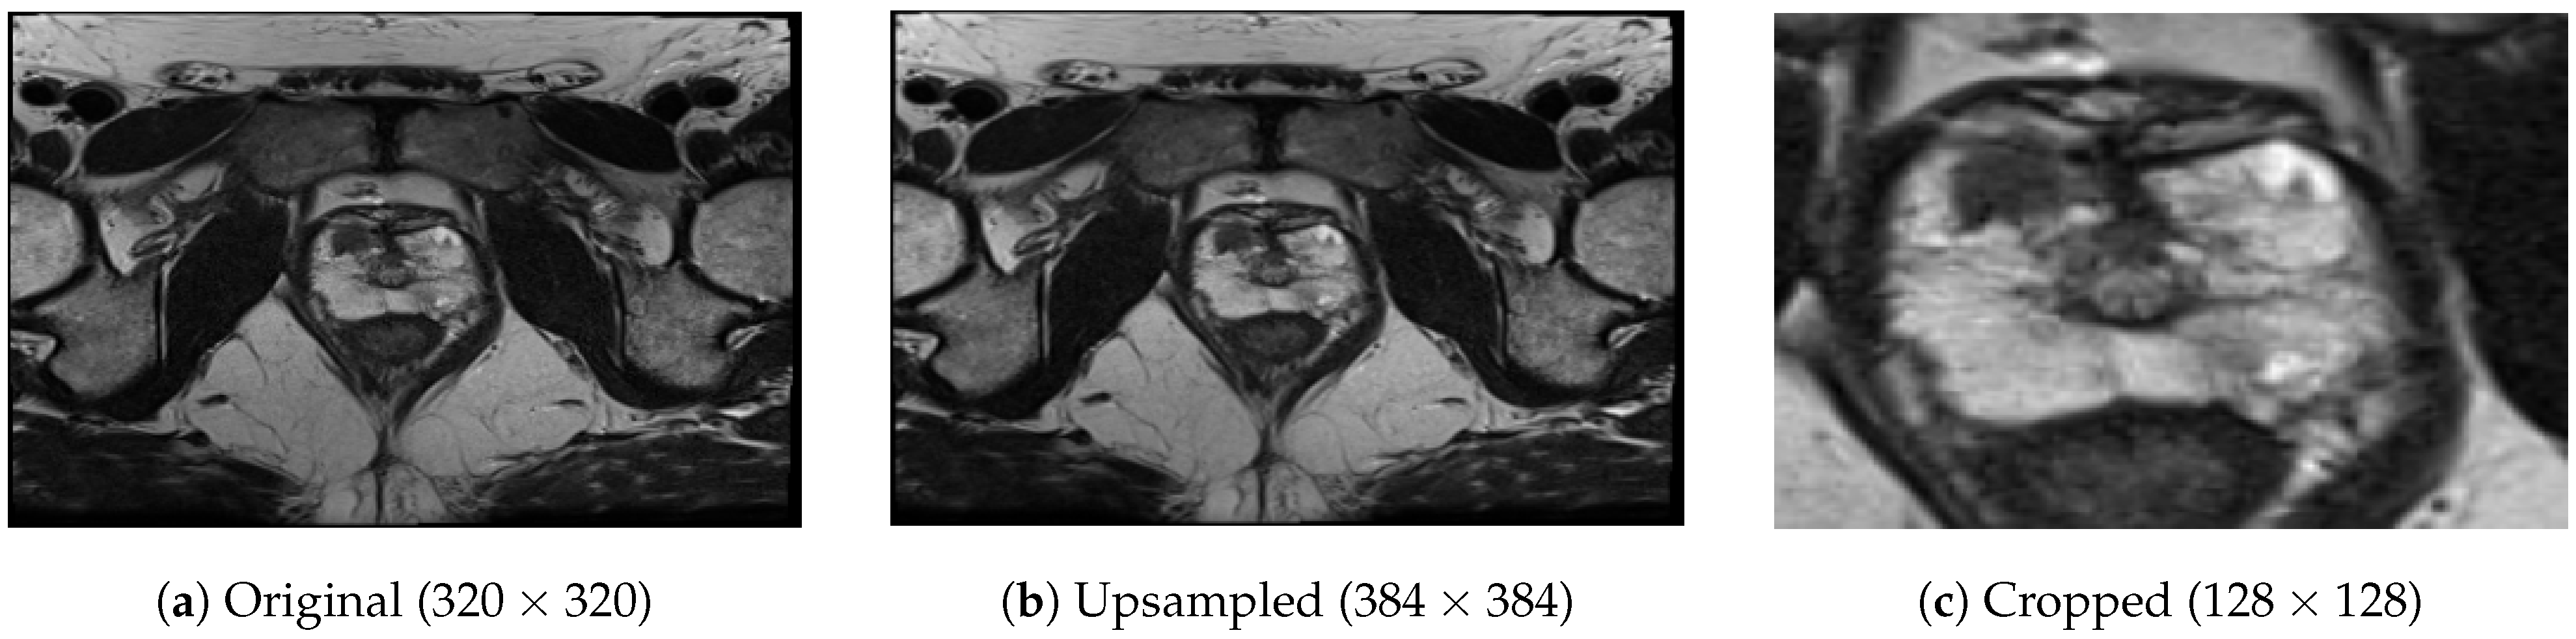

To address the issue of varying matrix sizes in the dataset (in terms of the number of pixels in rows and columns), we adopted a resampling approach. In particular, we selected the largest and most common matrix dimension as our reference size, which was 384 × 384 in this case, and we upsampled all the images, utilizing bilinear interpolation to match the reference size. This resampling technique allowed us to standardize the image dimensions across the dataset. The decision to choose the largest matrix dimension as the reference in our study was driven by two main considerations. Firstly, by selecting the largest matrix dimension, we aimed to minimize the need for down-sampling, thereby avoiding potential loss of valuable information that may occur during this process. Secondly, this choice was aligned with the most common size found in the dataset, reducing the number of patients that would require resampling. Another crucial aspect was that all acquisitions in the dataset shared the same slice thickness of 3 mm, eliminating the need for any modifications.

After upsampling the images to a consistent size of 384 × 384 pixels, we performed a center-cropping operation on each slice to facilitate the model’s focus on the prostate gland. The center-cropping process involved extracting a smaller region from the center of each slice. Through empirical analysis, we determined that a crop size of 128 × 128 pixels was suitable for encompassing prostate glands of various sizes within the field of view while eliminating a significant portion of non-glandular tissues. Thus, for each lesion, we obtained a volume of 128 × 128 × 5 pixels, representing the cropped slices from the selected region. In Figure 3, we provide an example of an image during the intermediate steps of upsampling and cropping.

Figure 3. Image examples during intermediate pre-processing steps.